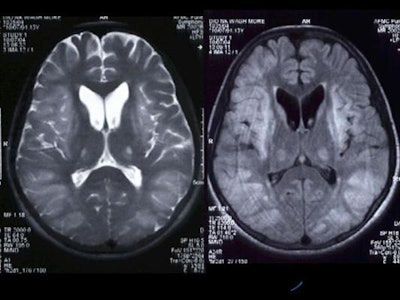

Diffuse hyperintensity at the cortex of both cerebral hemispheres on T2W and FLAIR images, with sparing of the white matter, was present [Figure 4]. These regions appeared mildly hypointense on T1WI. Mild sulcal effacement is seen in the involved regions.